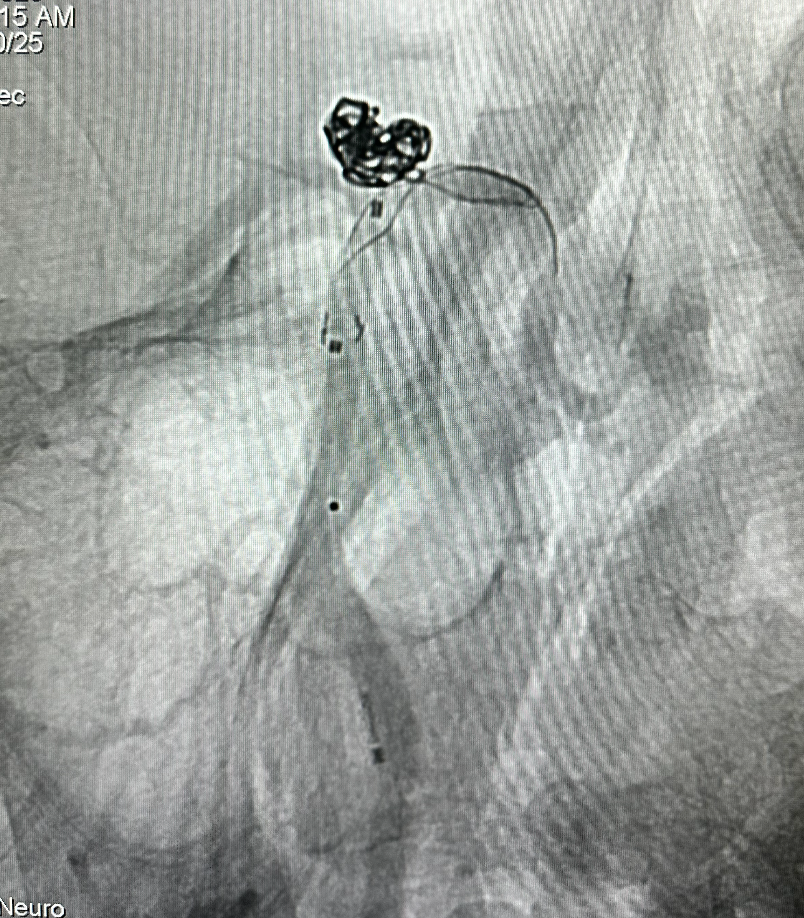

继续释放并调整 畅医达(TaminoVIA)颅内动脉瘤辅助栓塞支架 至合适位置,支架两端为闭环设计,操作过程中能减少血管壁损伤,瘤颈处部分推密增加金属覆盖率

畅医达(TaminoVIA)颅内动脉瘤辅助栓塞支架完全释放,打开效果好,显影清晰,瘤体部分显影

患者高龄,瘤体破裂出血风险降低,考虑编织支架修复作用,未继续填塞弹簧圈

术后造影显示动脉瘤囊闭塞,畅医达(TaminoVIA)颅内动脉瘤辅助栓塞支架形态良好,载瘤动脉通畅